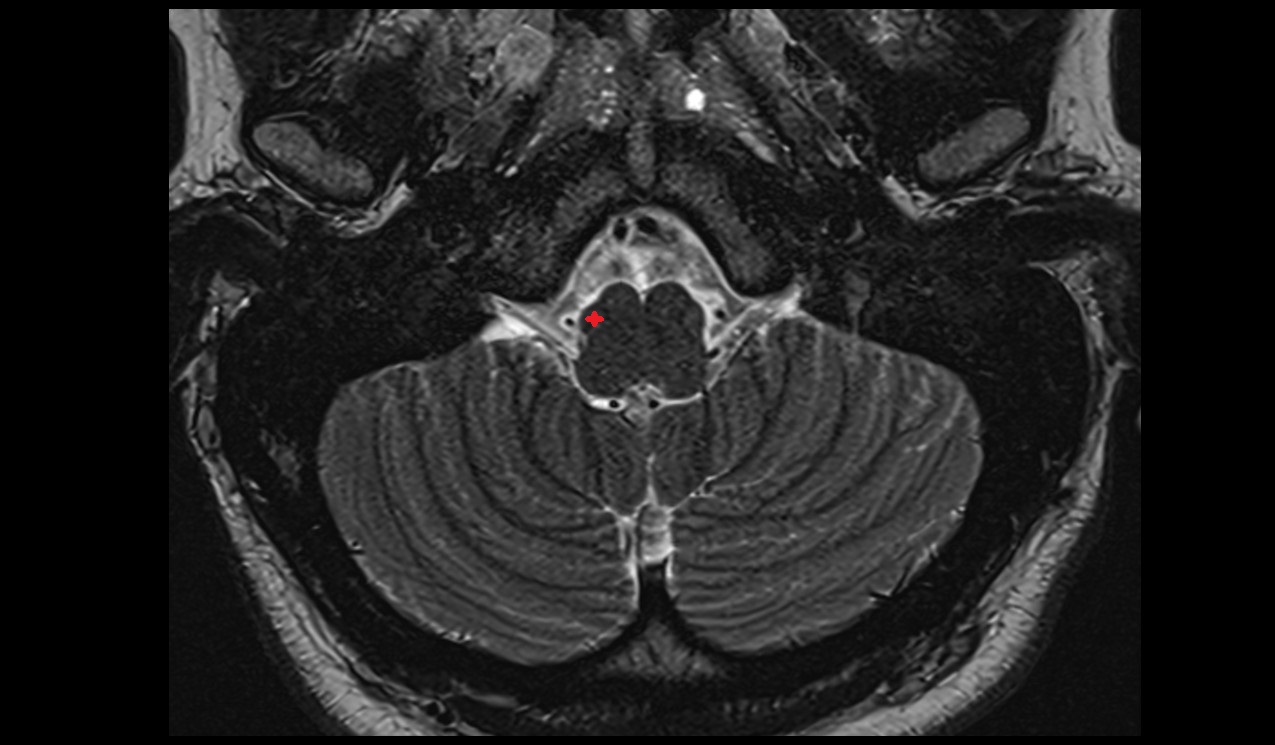

- Cerebellum

- Cerebellar tonsil (H IX)

- Cisterna magna

- Posterior cerebellomedullary cistern (cisterna magna)